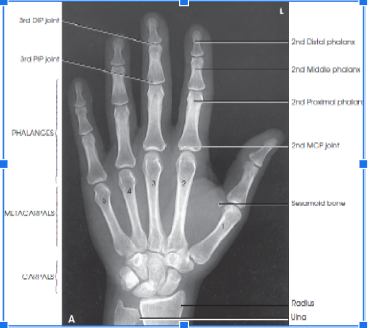

anatomy from fingertips to distal radius and ulna

slightly separate digits with no sift tissue overlap

equal concavity of the metacarpal and phalangeal bodies

equal amount of soft tissue on both sides of the phalanges

equal distance between the metacarpal heads

the nail

MCP and IP joints. It indicates that the hand is flat on the IR